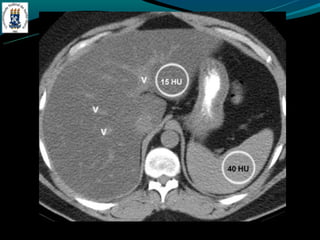

HEMOCROMATOSE

-Primária(hereditária)

-   Aumento da reabsorção gastrointestinal

-   4ª e 5ª década de vida

-   DM, IC, artralgia…

-Secundária(aumento do aporte)

-   Anemia crônica com múltiplas transfusões

-   Ingestão excessiva, porfiria,

-TC: fígado com densidade > 70 HU – sobrecarga de ferro

-Ouro coloidal, doença de Wilson, d. armaz. de glicogênio

-RM: Redução da intensidade do sinal em T1 e T2. hiperintenso

no baço.

-Hemossiderose, d. de Wilson…

HEMOCROMATOSE -Primária(hereditária) - Aumento da reabsorção gastrointestinal - 4ª e 5ª década de vida - DM, IC, artralgia… -Secundária(aumento do aporte) - Anemia crônica com múltiplas transfusões - Ingestão excessiva, porfiria, -TC: fígado com densidade > 70 HU – sobrecarga de ferro -Ouro coloidal, doença de Wilson, d. armaz. de glicogênio -RM: Redução da intensidade do sinal em T1 e T2. hiperintenso no baço. -Hemossiderose, d. de Wilson…